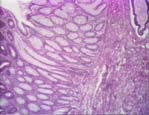

| adenomatous polyps | term type: main entry term part of speech: noun number: singular reliability code: 9 definition: small, non-hereditary, noncancerous growths in the intestines that might be invasive if not treated appropriately. If they are large and obstruct the passage of waste material, they can cause intermittent bleeding. About 5% of adenomatous polyps become cancerous. (en) context (x): Adenpol.txt origination date: 17/10/2001 |

| pólipos adenomatosos | term type: main entry term part of speech: noun gender: masculine number: plural reliability code: 9 definition: pequeños tumores benignos y no heredados que aparecen en el intestino y que pueden convertirse en cancerosos si no son tratados adecuadamente. Cuando por su tamaño obstruyen la salida de desechos orgánicos, pueden causar hemorragias intermitentes. Cerca de un 5% de los pólipos adenomatosos se convierten en cancerosos. (es) context (x): Poladen.txt origination date: 22/10/2001 |